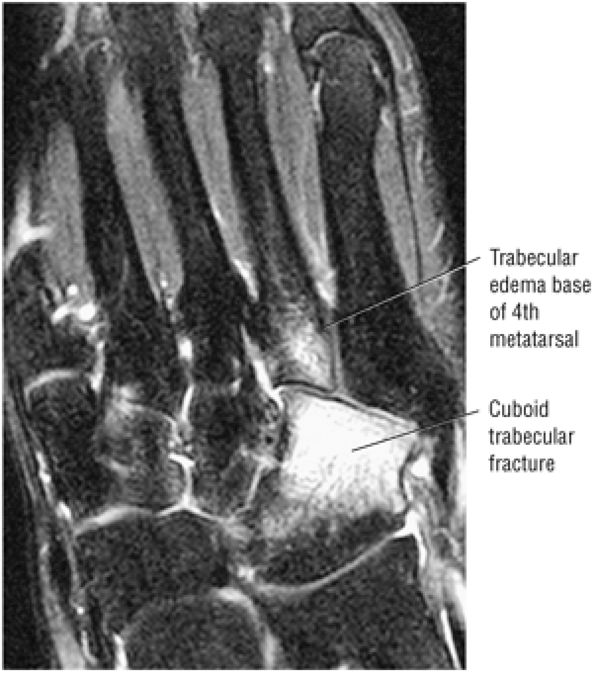

FIGURE 5.27 ● Axial anatomy of the ankle and foot. (A) The flexor digitorum longus, flexor hallucis longus, peroneus brevis, soleus, and extensor digitorum muscles are examined at this level for strain, tears, or fatty atrophy that may suggest denervation. (B) The tibialis anterior, extensor hallucis longus, and extensor digitorum longus tendons are examined on every ankle MR examination. Extensor tendon pathology is frequently overlooked if these tendons are not included as part of the ankle checklist. (C) Tears and sprains of the anterior syndesmotic ligament are a frequent cause of persistent ankle pain following ankle sprain. The syndesmotic ligaments are thick, tough ligaments that are important ankle stabilizers, and delayed diagnosis of syndesmotic tears may result in significant degenerative arthrosis at the tibiotalar joint due to the resulting ankle instability. The syndesmotic ligaments course obliquely inferiorly from the tibia to the fibula and are not usually visualized in their entirety on a single axial image; rather, their course is followed on at least two or three successive axial images. (D) The peripheral margin of the peroneal tendons and tibialis posterior tendon should normally never extend beyond the peripheral margins of the lateral and medial malleoli, respectively. Tendon subluxation around the posterior corner of either malleolus is indicative of a tear of the overlying flexor retinaculum (medially) or peroneal retinaculum (laterally). When the retinacula are torn, the tendon is free to intermittently sublux or dislocate, leading to tendon degeneration, pain, and tendon dysfunction. (E) Suspected osteochondral lesions of the talar dome are visualized and further characterized on axial images through the top of the talar dome. (F) The peroneus brevis tendon may normally appear somewhat flattened. However, as the tendon degenerates, it becomes U-shaped and drapes around the anterior aspect of the peroneus longus and becomes impinged between the peroneus longus tendon and the lateral malleolus. With further degeneration, the peroneus brevis may split or completely rupture. (G) Evidence of anterior talofibular ligament injury is visualized on the majority of MR ankle examinations and appears as thickening, intermediate signal with ill-defined fibers, or attenuation of the ligament. This is commonly asymptomatic. (H) Because the flexor hallucis longus tendon sheath communicates with the tibiotalar joint, fluid may normally be present within the tendon sheath in proportion to the amount of fluid in the tibiotalar joint. If there is fluid within the tendon sheath out of proportion to that seen in the tibiotalar joint, tenosynovitis is most likely present. The finding of flexor hallucis longus tenosynovitis should prompt a search for an os trigonum, as impingement of the flexor hallucis longus tendon between an os trigonum and the posterior tibial plafond is a common cause for FHL tenosynovitis. (I) The calcaneofibular ligament (CFL) passes anterior and medial to the peroneal tendons. On the image at which the CFL passes directly medial to the peroneus brevis tendon, the appearance of the peroneus brevis and the CFL side by side is occasionally mistaken for a split peroneus brevis tendon. (J) Dilated posterior tibial veins within the tarsal tunnel occasionally compresses the tibial nerve. In the setting of clinical suspicion for tarsal tunnel syndrome or if there is evidence of muscle denervation on MR images, the size of the posterior tibial veins should be described. (K) The spring ligament is identified at this axial image location, extending from the anteromedial calcaneus to the posteromedial navicular. Tears of the spring ligament may result in medial instability and hindfoot valgus. (L) The posterior tibialis tendon (PTT) may normally become thickened and fan-like as it passes posterior to its navicular insertion (prior to also inserting on the cuneiforms and the base of the second through fourth metatarsals). In the absence of other findings, the thickening of the PTT at this level should not be mistaken for focal tendinosis. (M) On inferior images through the ankle, Lisfranc's ligament is occasionally included in the FOV. Lisfranc's ligament extends from the medial cuneiform to the base of the second metatarsal. If Lisfranc's ligament is included in the FOV, the status of the ligament should be described, as undiagnosed Lisfranc ligament tears can lead to debilitating midfoot arthrosis. (N) As the medial and lateral tendons turn from their vertical course to a horizontal course along the plantar aspect of the foot, the tendons may demonstrate a magic-angle artifact, causing the tendons to appear gray on short-TE images, mimicking tendinosis. Correlation with images using longer TE values is advised in such situations.